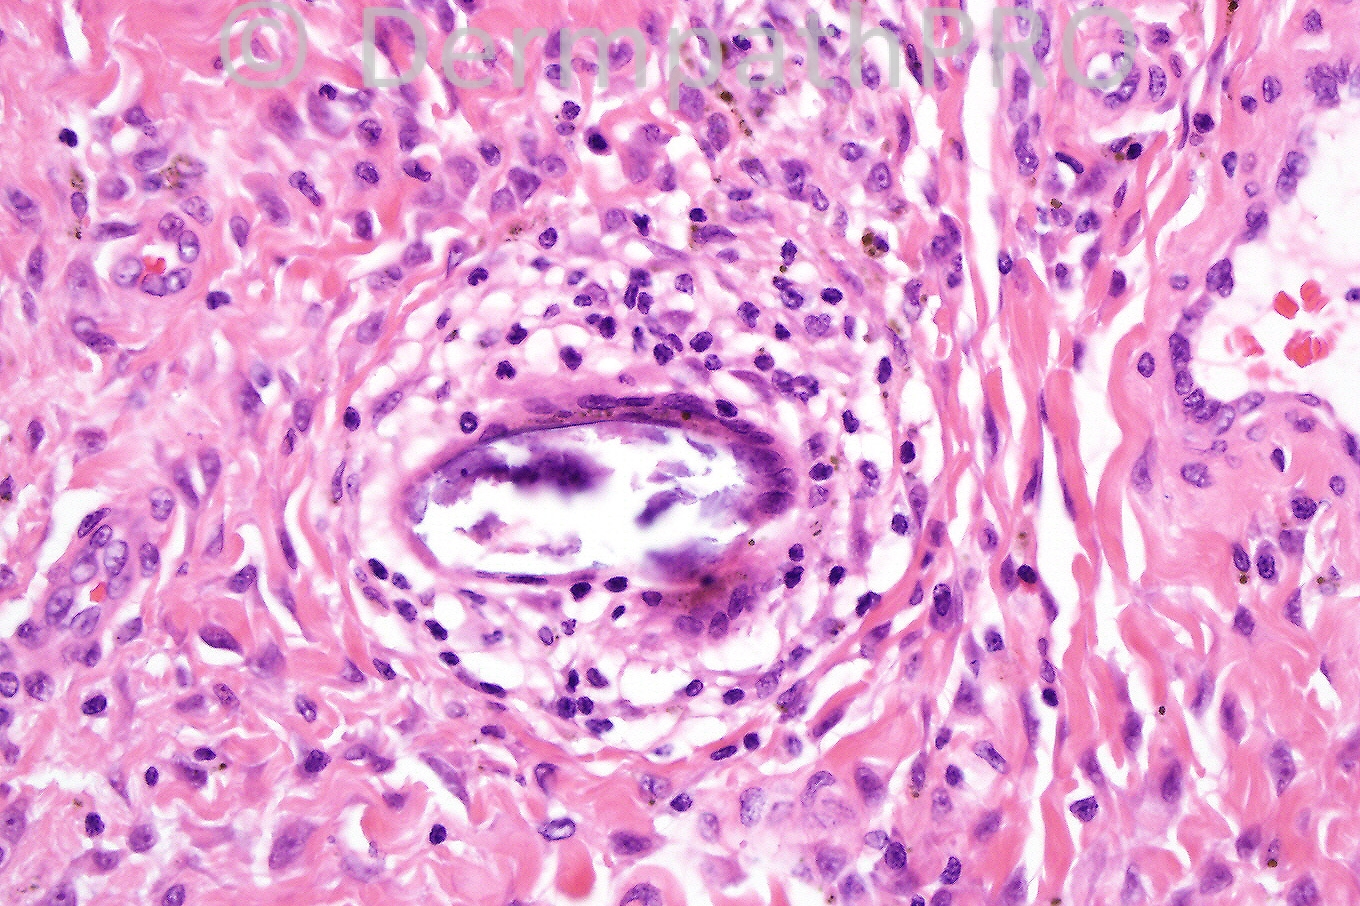

Female 33 years, vulval nodules.

The diagnosis is cutaneous Schistosomiasis. No extra marks for the Egyptian dermatopathologists and for that matter anyone from SA! Regards

CUTANEOUS SCHISTOSOMIASIS (VIABLE AND CALCIFIED OVA).